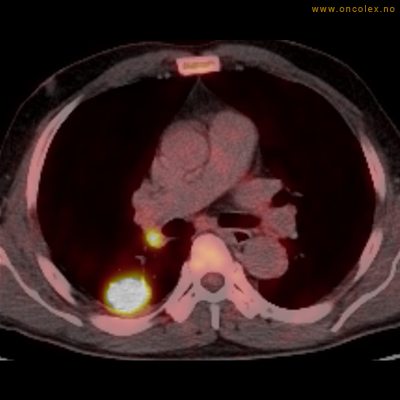

Vev som tar opp mer radioaktivt stoff, synes som hvite områder som lyser opp mer i forhold til annet vev som tar opp mindre sukker.

Adenokarsinom distalt i spiserør. Fysiologisk opptak i hjertemuskulatur.

Adenokarsinom langt nede i spiserøret.